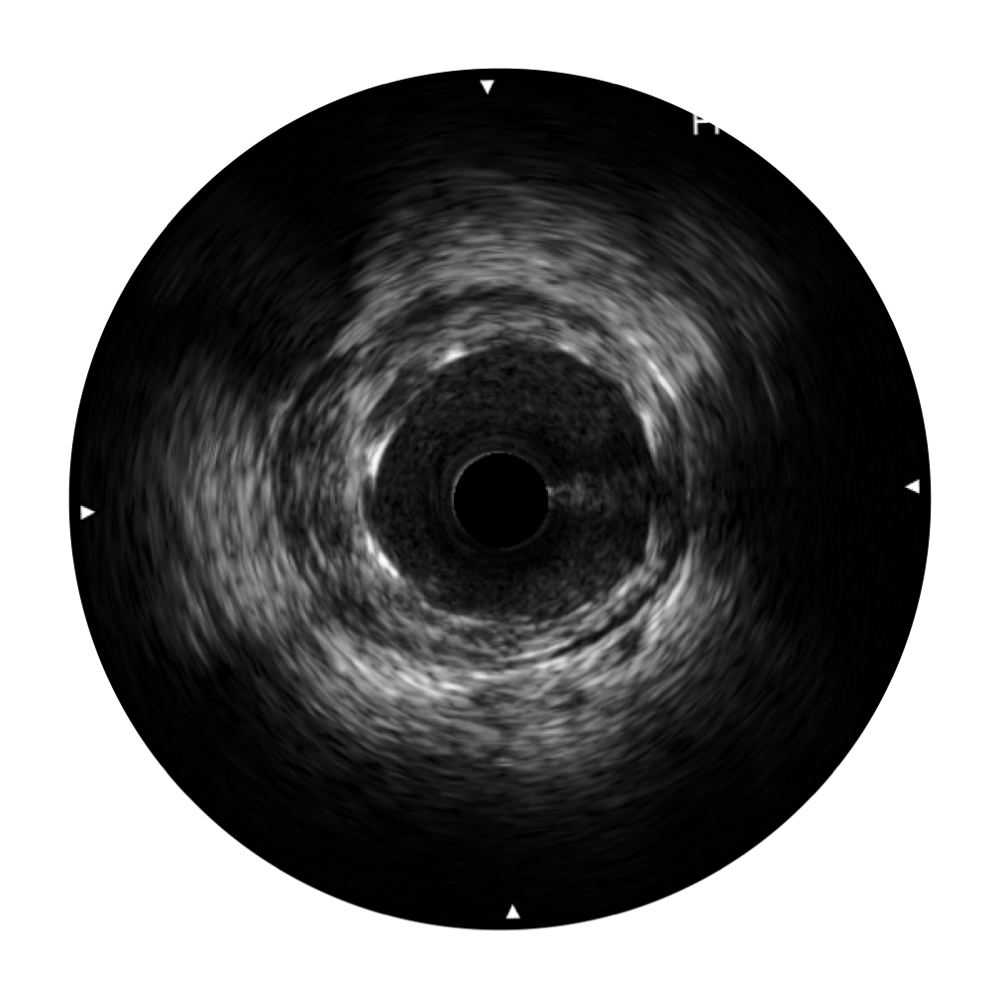

血管内超声(IVUS) 通过对病变程度、性质和累及范围的精确判断,可帮助选择治疗策略和方法,指导介入治疗过程,能够降低主要不良心血管事件,改善预后,在复杂病变介入治疗中用于指导支架置入的优势更为明显。血管内超声(IVUS)已成为精准心血管介入治疗的“金标准”。

狗万官方网站超宽频成像技术覆盖20-80MHz1或20-90MHz2频率范围, 提供优异的分辨力同时也保证充足的穿透深度

对比传统IVUS导管成像,狗万官方网站宽频IVUS图像的近场支架梁显影更细腻,远场中膜外血管仍清晰可辨,兼顾远中近,兼顾分辨力与穿透深度